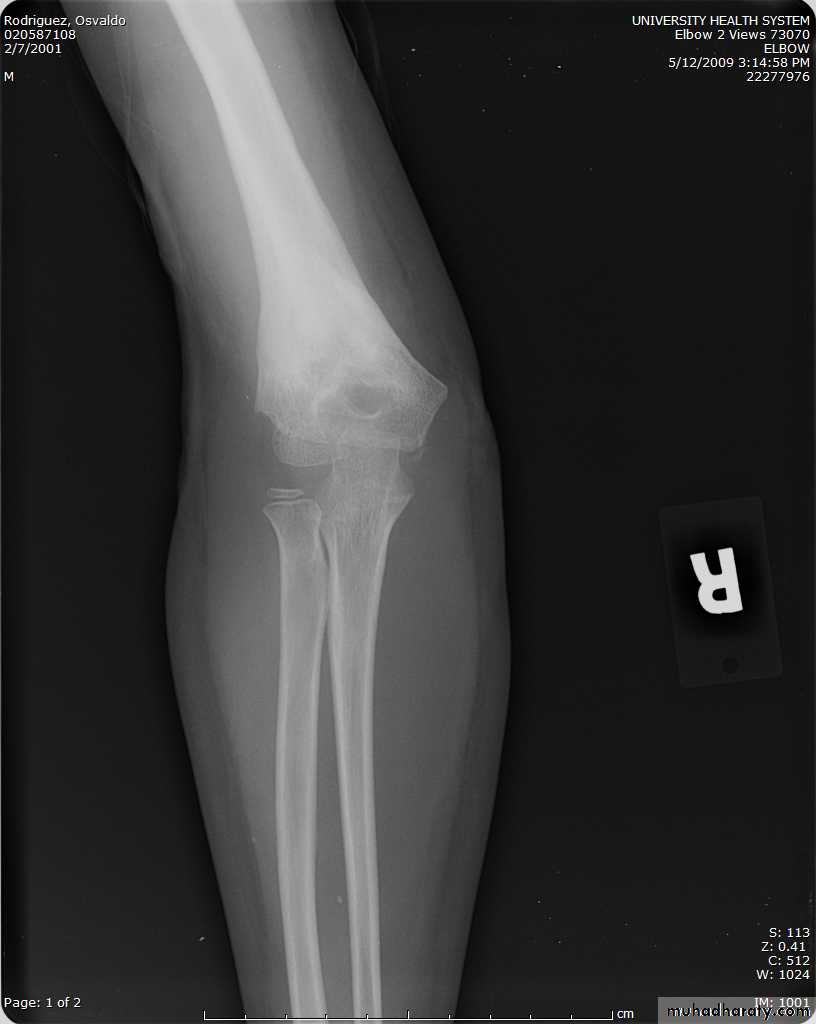

How are we going to stabilize this boy’s fracture?

Antegrade Flexible I M NailsOur Patient P.O.

Probably acts more

as an internal splintSix months post-operative

How is he doing clinically?